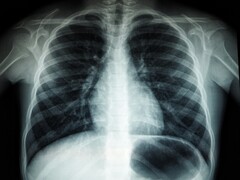

Les chercheurs indiquent qu'une seule séance de coiffure de 10 à 20 minutes peut entraîner l'inhalation de plus de 10 milliards de nanoparticules. Selon eux, ce niveau de pollution est comparable à celui que l'on rencontre au milieu d'un trafic autoroutier dense. Compte tenu de leur taille, ces particules peuvent facilement pénétrer profondément dans les poumons. Cela peut entraîner des problèmes de santé tels que le stress respiratoire, l'inflammation des poumons et le déclin cognitif.